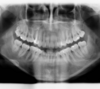

Rédicive d'un traitement dans l'enfance repris avec des gouttières

A-Début